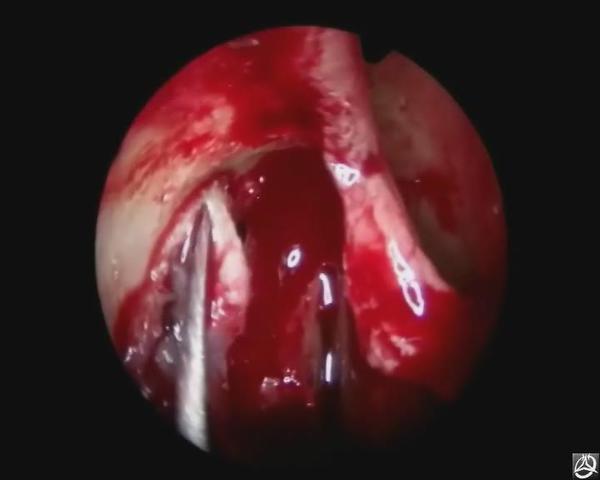

鼻内镜手术,操作方法步骤,图片图解,手术图谱,鼻部手术,手术治疗实例,鼻使鼻腔、鼻窦,尤其是深部的手术能

慢性鼻窦炎内视镜手术治疗 用鼻窥镜检查正常鼻腔—在线播放—《用鼻窥镜检查正常鼻腔》—生活—优酷网,

娄底爱尔眼科医院鼻内窥镜下鼻腔泪囊吻合术

慢性泪囊炎的微创手术治疗--鼻内镜下鼻腔泪囊